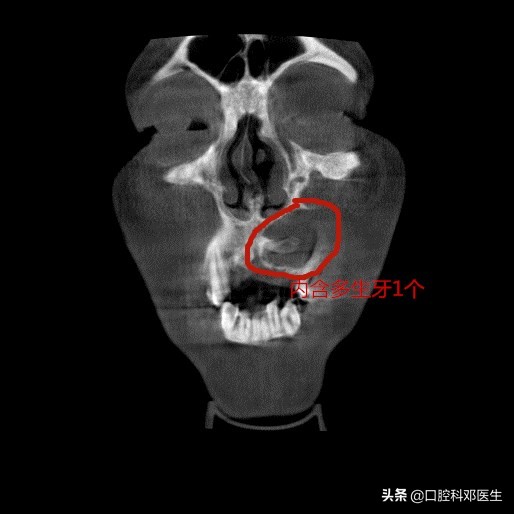

冠状位片

接诊的邓医生介绍:这位患者脸肿大是由于左侧上颌骨内一个埋伏多生的牙齿所引起的,由于牙齿无法正常萌出,经过时间的积累,从而诱发囊肿,囊肿一般都不痛不痒,越长越大,像鼓气球一样,逐渐破坏了周围的骨头,如破坏上颌骨前壁,就会突破至软组织,引起脸部肿大;如破坏牙槽骨,则会导致牙齿松动移位,引起牙根吸收疼痛等症状。

深位埋伏的阻生智齿可形成牙原性颌骨囊肿,高位阻生齿可因创伤颌而引起颞颔关节病,此外很多不明原因的面部疼痛都有埋伏牙有一定的关联。